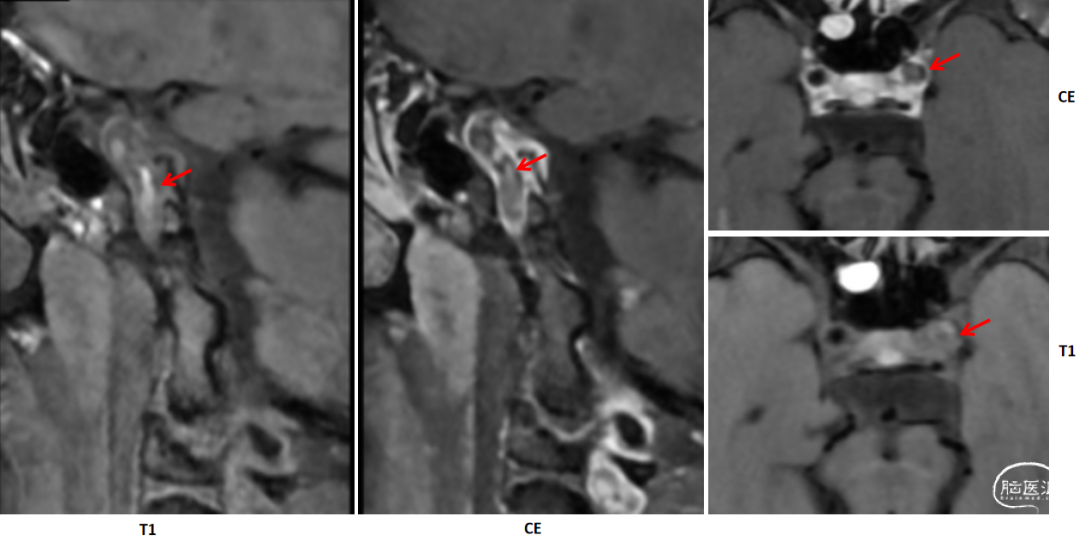

2024-09-04 HR-MRI:

3D-TOF-MRA提示左侧颈内动脉闭塞,T1等稍高混杂信号,CE不均匀强化,未见明确正性、负性重构。考虑不稳定斑块或血栓。

T1

CE

L-C5段:T1高信号,CE不均匀强化,考虑血栓。